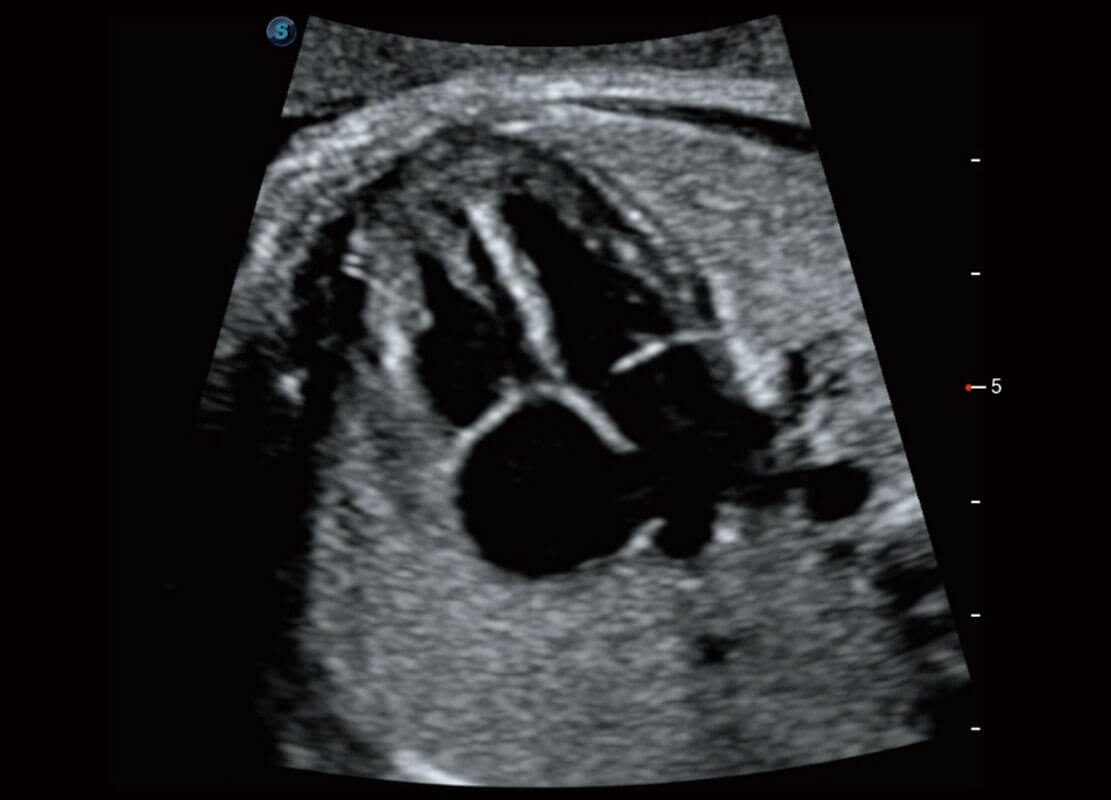

P60搭载一系列胎儿心脏成像技术,实现精细的胎儿心脏评估。

四腔切面